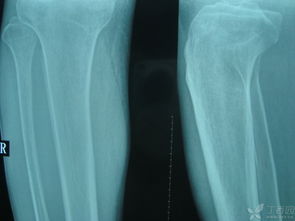

胫骨平台是位于胫骨上端的一个平台,与股骨的髁部形成膝关节。胫骨平台骨折是指胫骨平台部位发生的骨折,可能是由于直接撞击、跌倒或扭伤等原因引起。根据骨折的严重程度和位置,可分为多种类型,如单纯骨折、粉碎性骨折等。

并非所有胫骨平台骨折都适合保守治疗。以下情况可以考虑采用保守治疗:

无移位的胫骨平台骨折

胫骨平台关节面塌陷小于2mm